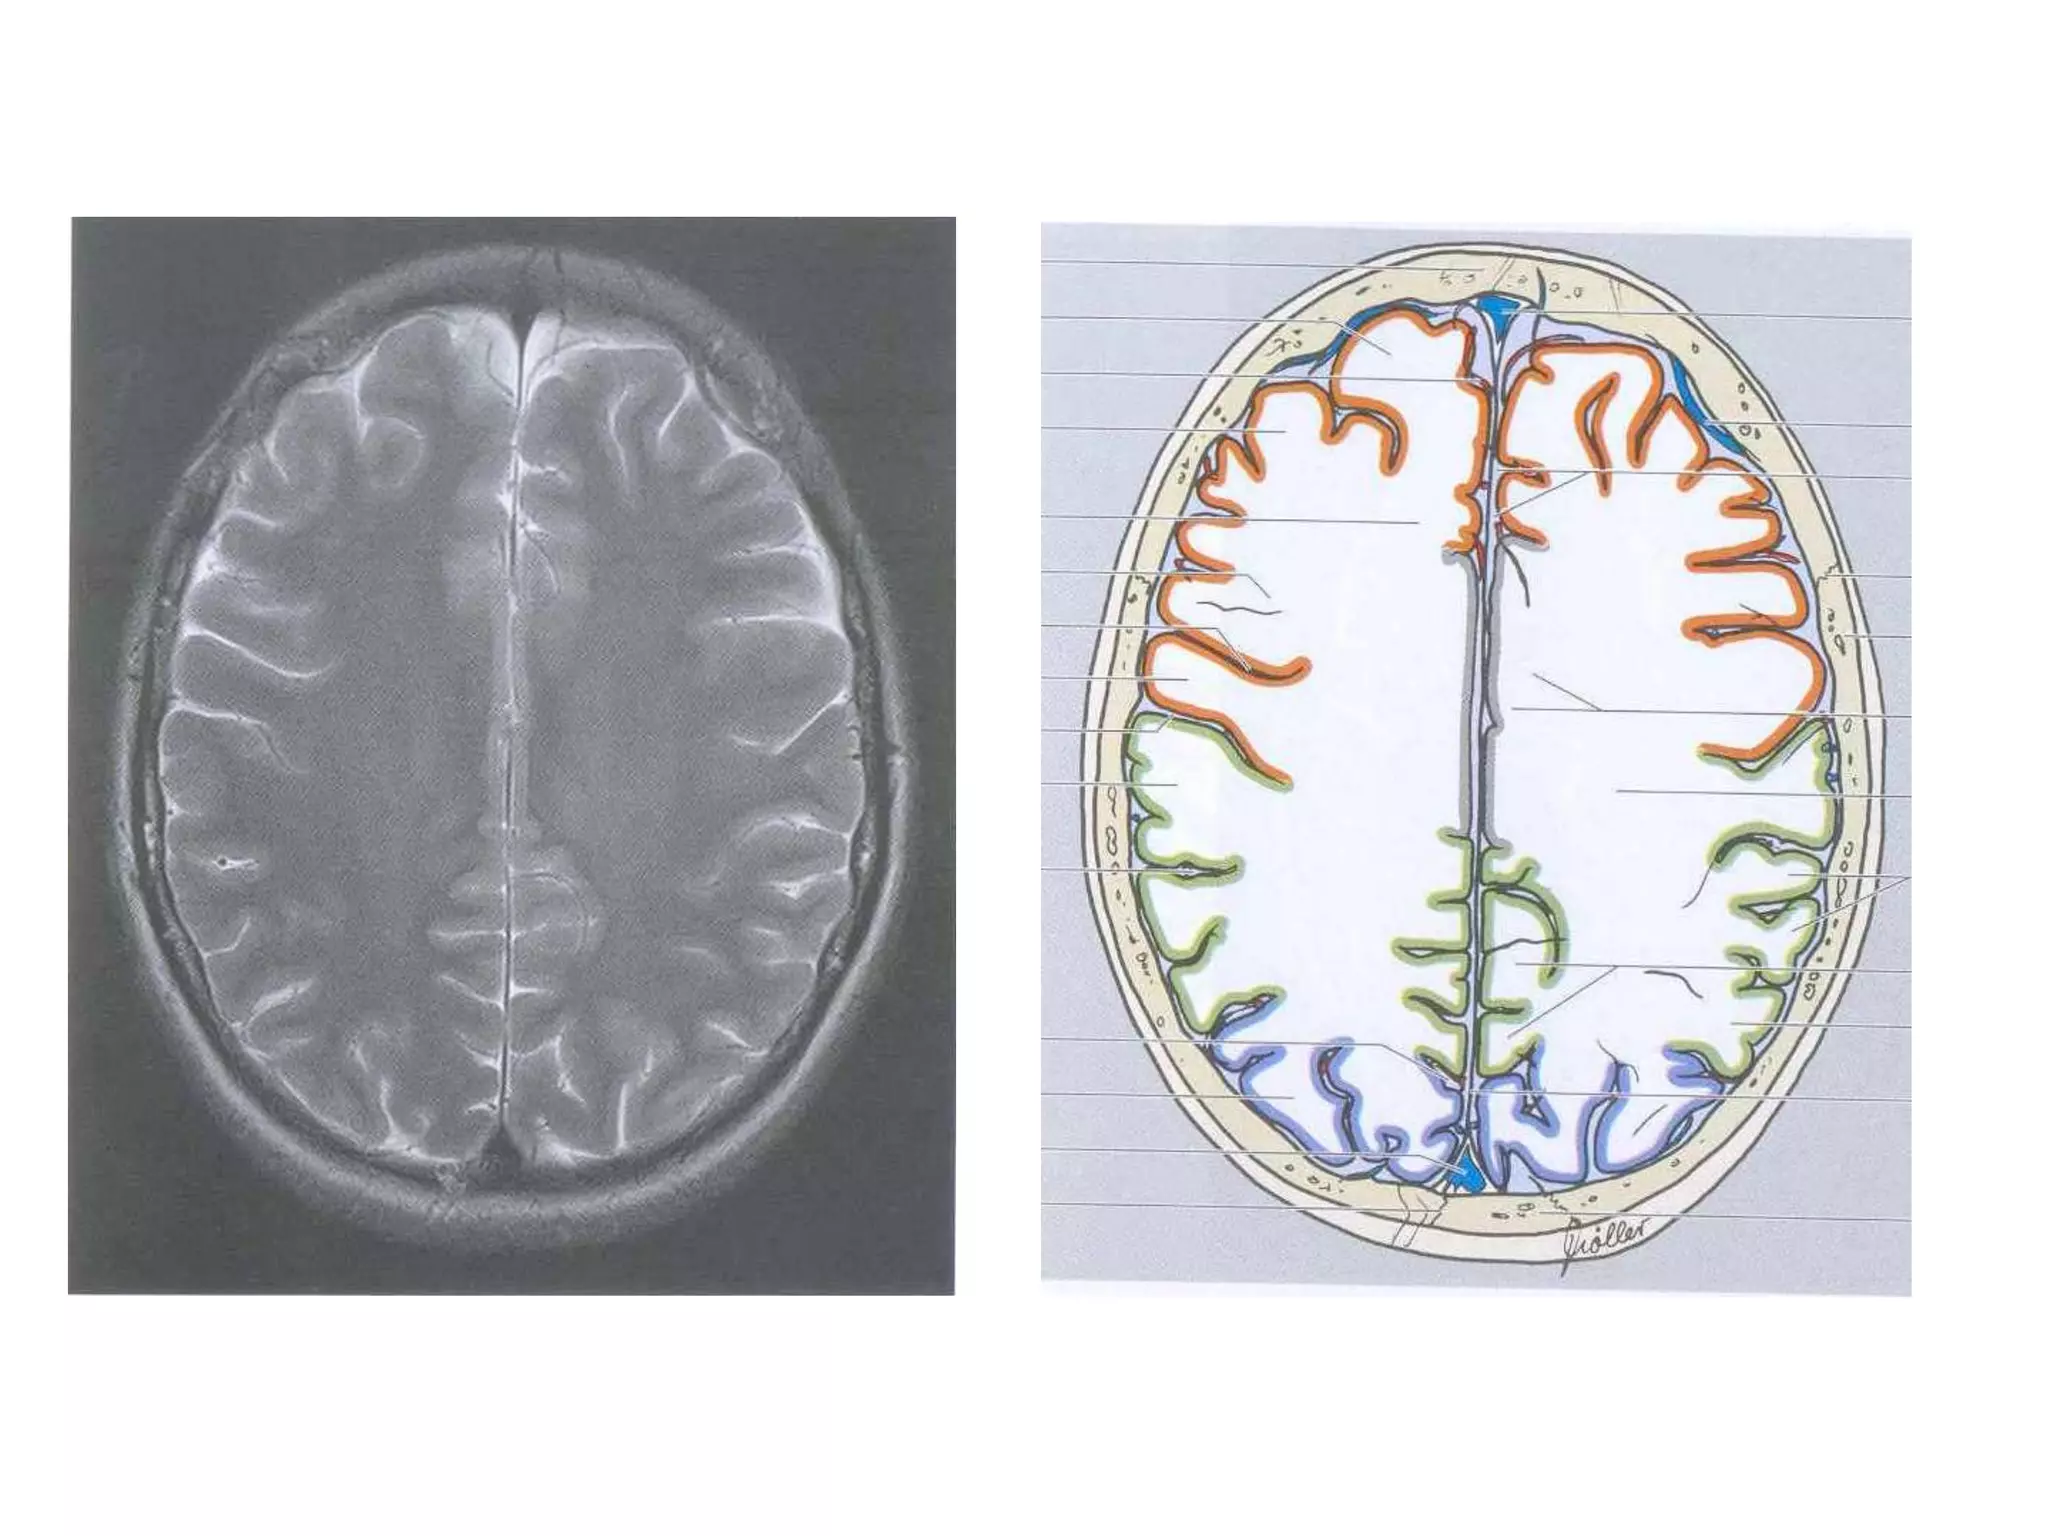

• In Cerebral hemispheres , white matter above the level of

lateral ventricles is called centrum semiovale

CEREBRAL HEMISPHERES • 4lobes are present in each hemisphere. They are demarcated by fissures. • Each lobe is again divided into gyri by sulci . They are named accordingly. • Anatomy of cerebral hemispheres and mid brain – T1 W MRI. • Internal grey - white matter areas – T2 W MRI. • In Cerebral hemispheres , white matter above the level of lateral ventricles is called centrum semiovale

• 19.

FISSURES 1. Central sulcus 2.Sylvian fissure 3. Calcarine sulcus (temporo-occipital fissure) 4. Parieto-occipital fissure : Seen medially. Better seen on midline saggital MRI.